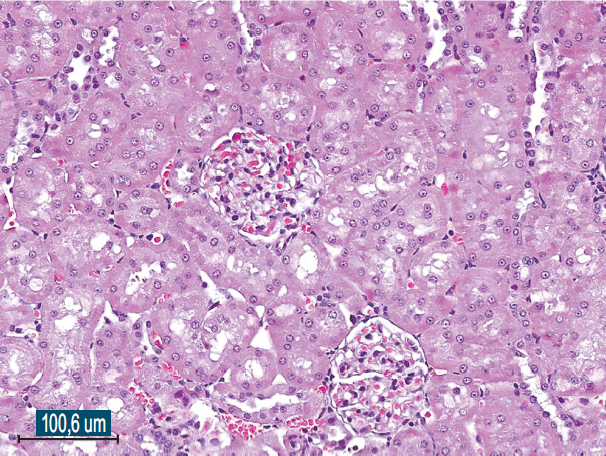

Histological examination of the removed paraurethral cyst was performed (Fig. 6–8).

Fig. 7.The wall of the paraurethral cyst, surgical material. Hematoxylin-eosin staining, ×100. Epithelium with signs of dystrophia and minimal desquamation are represented

Рис. 7.Стенка парауретральной кисты, операционный материал. Окраска гематоксилином и эозином, ×100. Эпителий с признаками дистрофии и минимальной десквамации